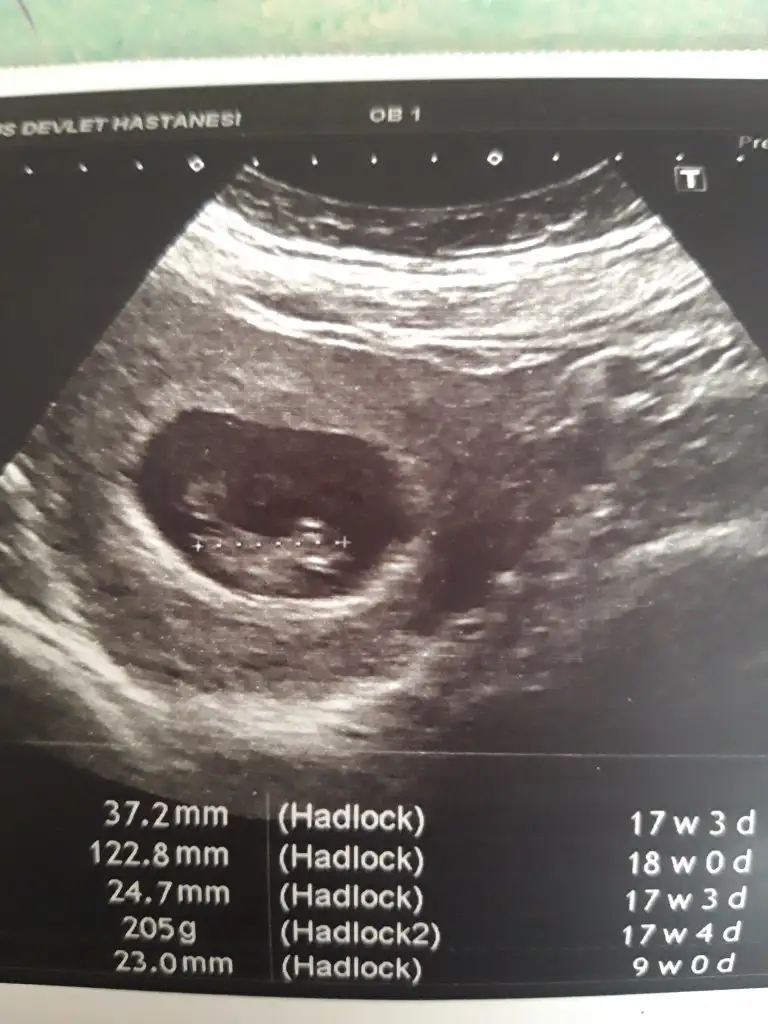

Slm kızlar adetime 2 gün kala b-hcg 171 çıkmıştı 6 gün sonra yani dün 2.256 çıktı. Bugün doktora gittim vajinal ultrasondan baktı ve kesemiz çok şükür gözüktü. Telefondaki uygulama 4+5 diyor ama doktor haftasıyla ilgili birşey demedi keseye odaklanmıstım soylemeyi unuttum kaç haftalık gözüküyor diye. Neyse kese iyi yerde etrafında kanama alanı yok dedi şükür. Pihtilasmadan dolayı kan sulandırıcı iğne kullanıyorum. Tsh değerim birazcık fırlamış onun içinde bir ilaç yazdı. Inşallah 2 hafta sonra kalp atışını da duyarım ve müjdeli haberi ailelerimize veririz inşallah. Daha söylemedik düşük olursa üzülürler diye. Allah'im hepimize sağlıklı bebisler nasip etsin. Sağlık sıkıntısı olan arkadaşlarıma da rabbim şifa versin çok geçmiş olsun diliyorum

• 20210326_131211.webp

20210326_131211.webp

27,3 KB · Görüntüleme: 57